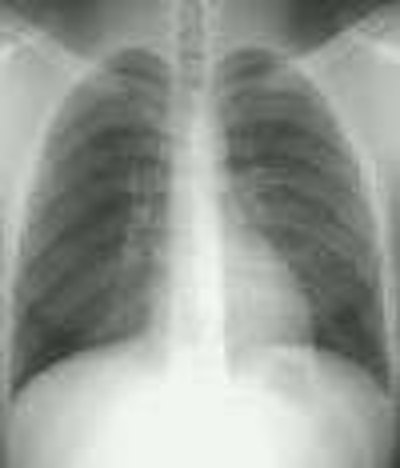

Morgagni Hernia:

The infant in the images below was referred for the evaluation of a "cystic anterior mediastinal mass." The "mass" was confirmed to be large bowel loops on a barium enema exam.

CXR: